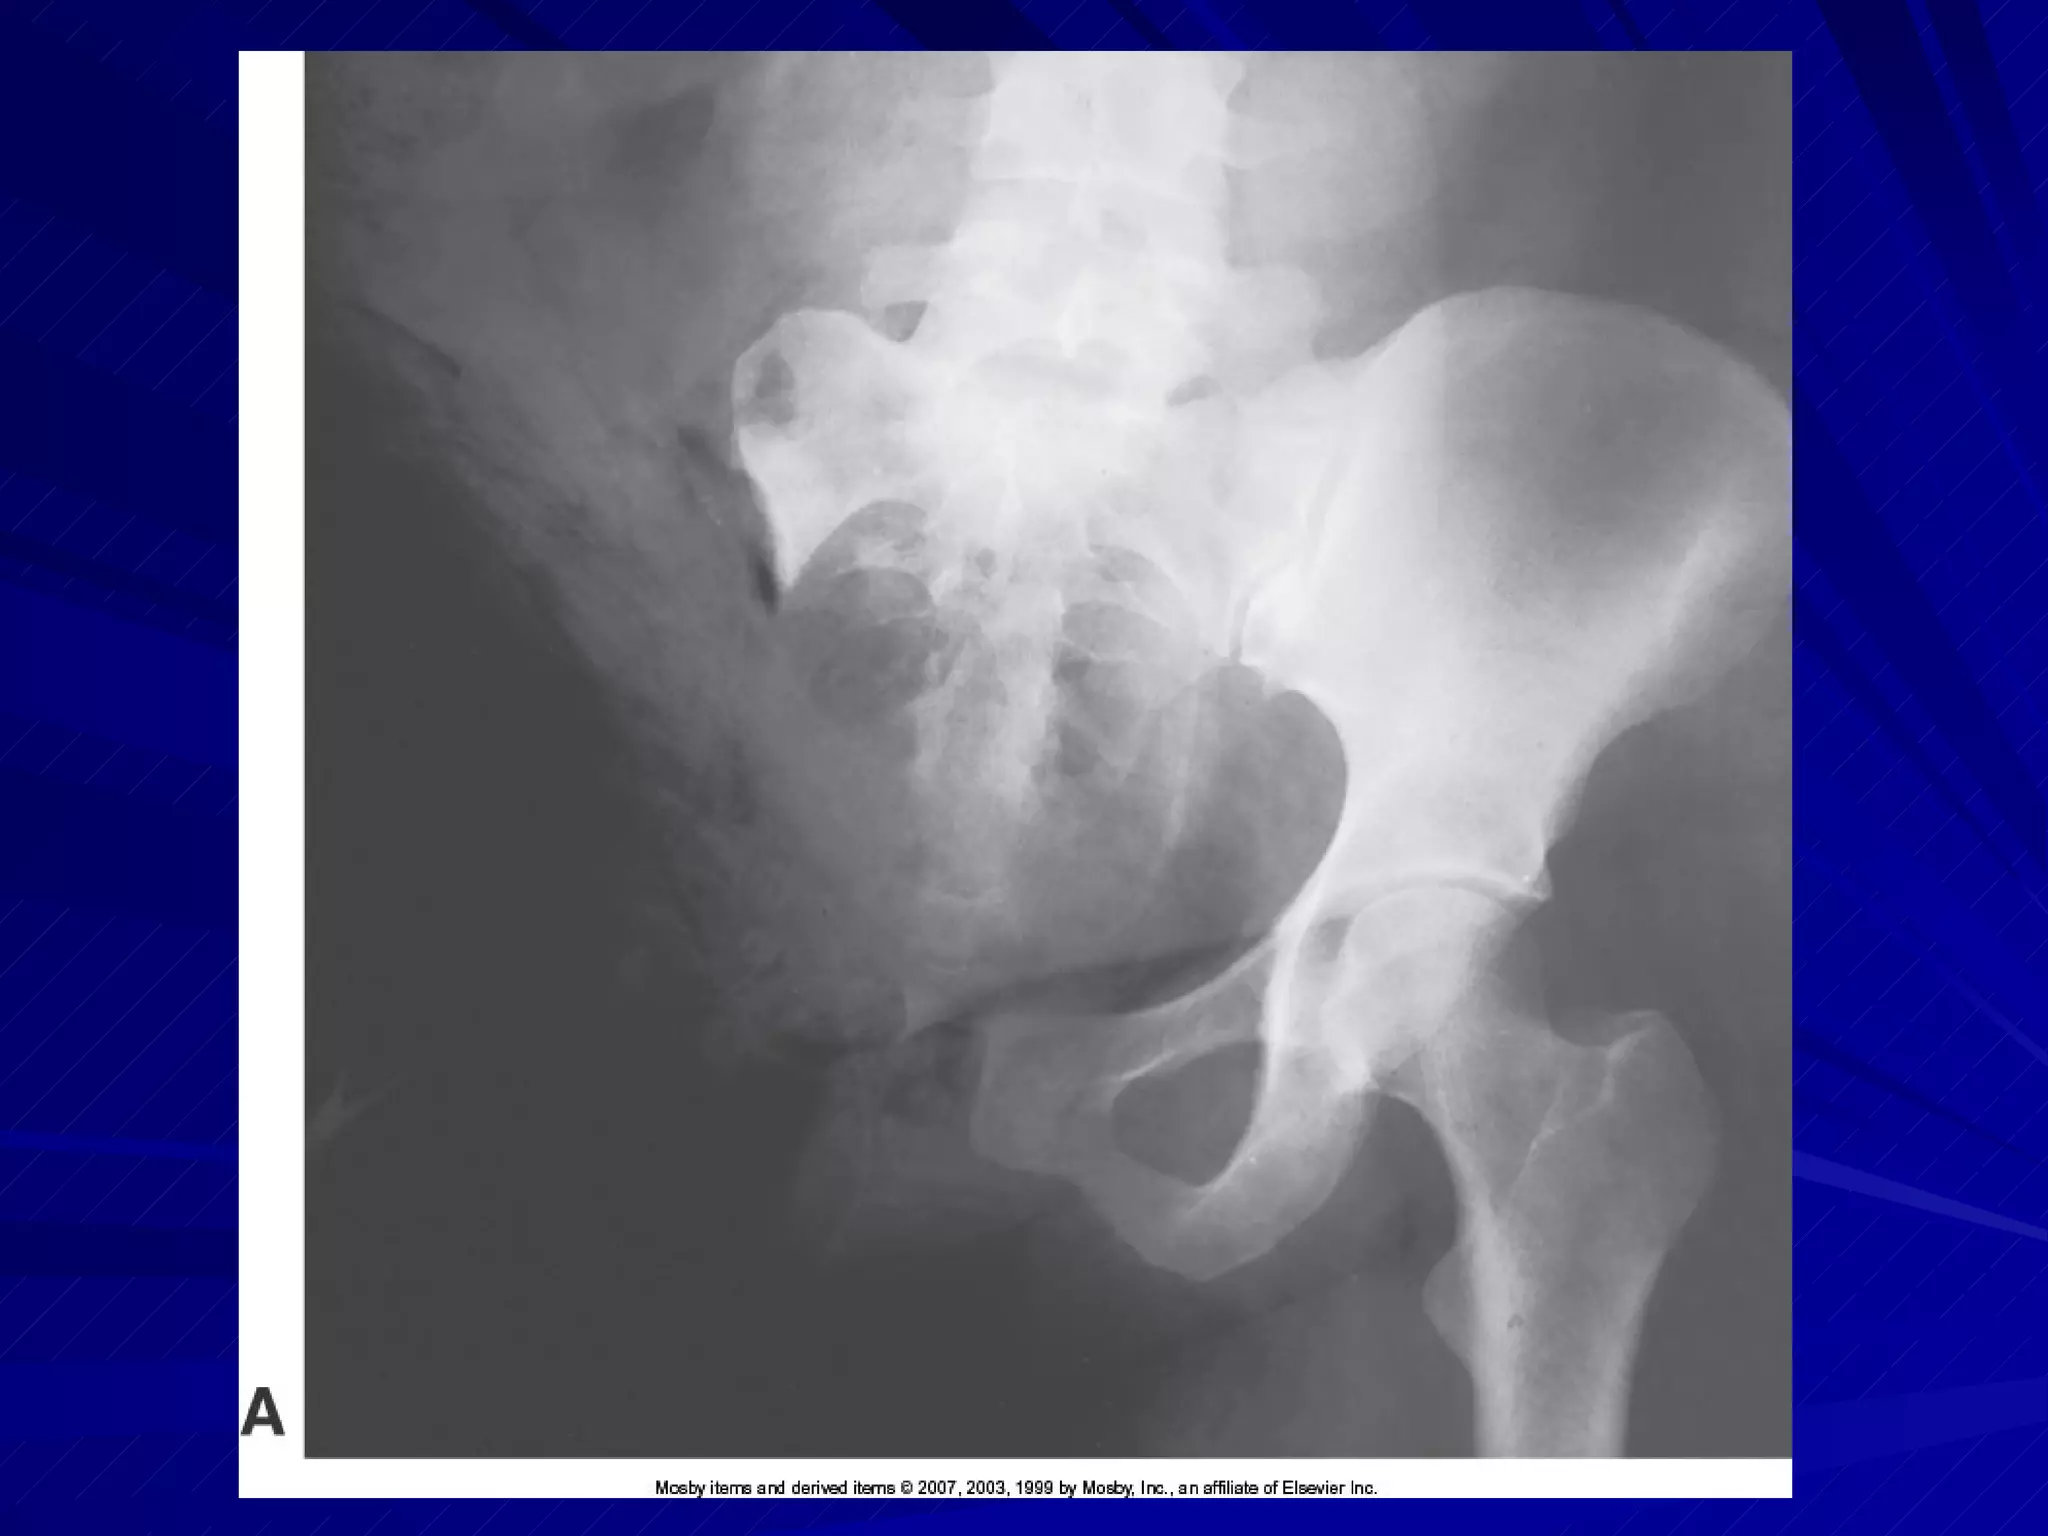

Trauma AP Pelvis Trauma AP pelvis; note fracture of left ilium and separation of pubic bones

Pelvis Pelvic fractureshave a high risk of hemorrhage – pay close attention to patient for status change Obtain lift help for IR placement if transfer to x-ray table is not possible IR centered 2  above pubic symphysis or 2  below ASIS MCP parallel to IR

Pelvis Lower limbsinternally rotated only if possible Ensure arms are not in anatomy of interest CR perpendicular to center of IR Exposure made on suspended respiration Image demonstrates entire pelvis and proximal femora

Trauma AP PelvisTrauma AP pelvis; note fracture of left ilium and separation of pubic bones